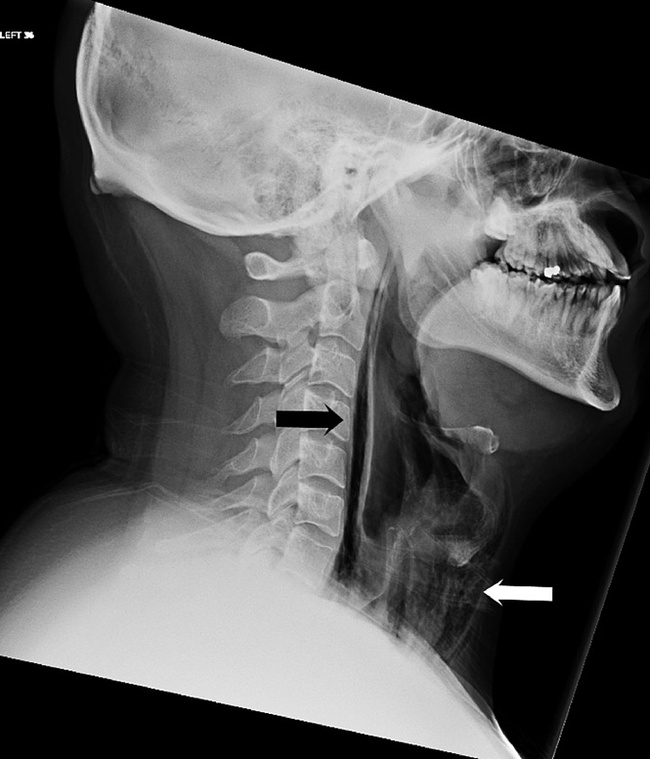

Рентген показал, что легкие не задеты, однако в мягких шейных тканях перед трахеей обнаружилось чрезмерное скопление воздуха. Компьютерная томография подтвердила: у больного обширная эмфизема в шее и грудной клетке, налицо была и перфорация глотки. Окончательный диагноз звучал зловеще: спонтанный разрыв пищевода, также известный как синдром Бурхаве. (Рентгеновский снимок шеи. Черной стрелкой показаны скопления воздуха, белой — обширная эмфизема перед трахеей.)